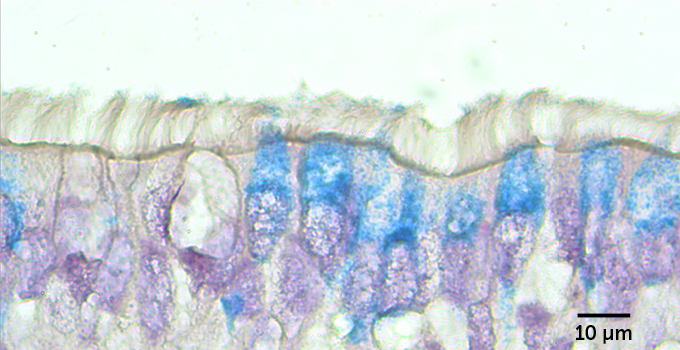

But not all the cells in the infected lawn were affected equally. Looking at the cells from the side, researchers could see that cells sporting cilia were infected with the coronavirus. But mucus-producing cells called goblet cells, which don’t have cilia, were rarely infected. That may be because a protein called ACE2 decorates the surface of ciliated cells far more often than it does goblet cells. ACE2 is the protein that the coronavirus uses as a door into cells.

All that extra mucus from the treated cells could ensnare viruses and expel them from the lungs before much damage is done. But people with nonallergic asthma and COPD make plenty of mucus too, and they aren’t protected from the virus. So Ehre and colleagues stripped away the mucus to see how the airway cells fared without this phlegmy trap.

That seems to be what it is doing for airway cells too. A thick layer of keratan sulfate developed on top of cells treated with IL-13, armoring them against a coronavirus infection.